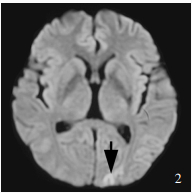

Dupont SA , Dispenzieri A , Mauermann ML , Rabinstein AA , Brown RD Jr . Cerebral infarction in POEMS syndrome: incidence, risk factors, and imaging characteristics. Neurology, 2009, 73: 1308- 1312.

doi: 10.1212/WNL.0b013e3181bd136b

Sugiyama A , Yokota H , Misawa S , Mukai H , Sekiguchi Y , Koide K , Suichi T , Matsushima J , Kishimoto T , Tanei ZI , Saito Y , Ito S , Kuwabara S . Cerebral large artery stenosis and occlusion in POEMS syndrome. BMC Neurol, 2021, 21: 239.

doi: 10.1186/s12883-021-02260-2